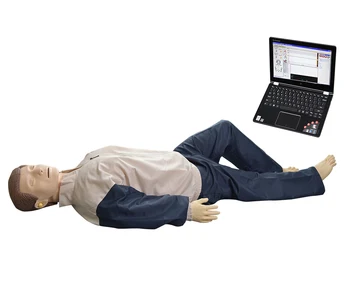

- GD/CPR10500 General Doctor Advanced CPR Simulator With Computer Control

$1,467.00 - $1,500.00/piece